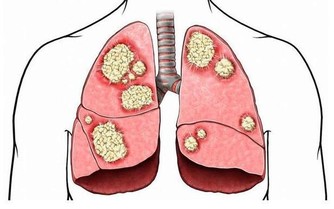

近期網絡上一篇報導引起了眾人們的關注,一位男性在體檢過程中檢查出患有脂肪肝。

眾人對脂肪肝的理解都是因為體內脂肪過多而導致的,

人們對於脂肪肝的常規理解就是大魚大肉比較多,油膩的東西進食太多,不愛運動,不良的生活方式等就成為了危險因素。如果全素食真的就可以和脂肪肝說拜拜了嗎?答案是:錯誤的,因為報導中的男子雖然是全素食飲食,但是絲毫沒有改變飲食中吃主食的習慣,數量反而增加了,這類人群的問題恰恰就出現在這個主食上面。

主食中的澱粉和醣類在滿足機體的需求之後,富裕出來的就會變成脂肪存積起來,如果脂肪過多,就會變成大眾理解的樣子,跑進肝臟裡面,引起脂肪肝。